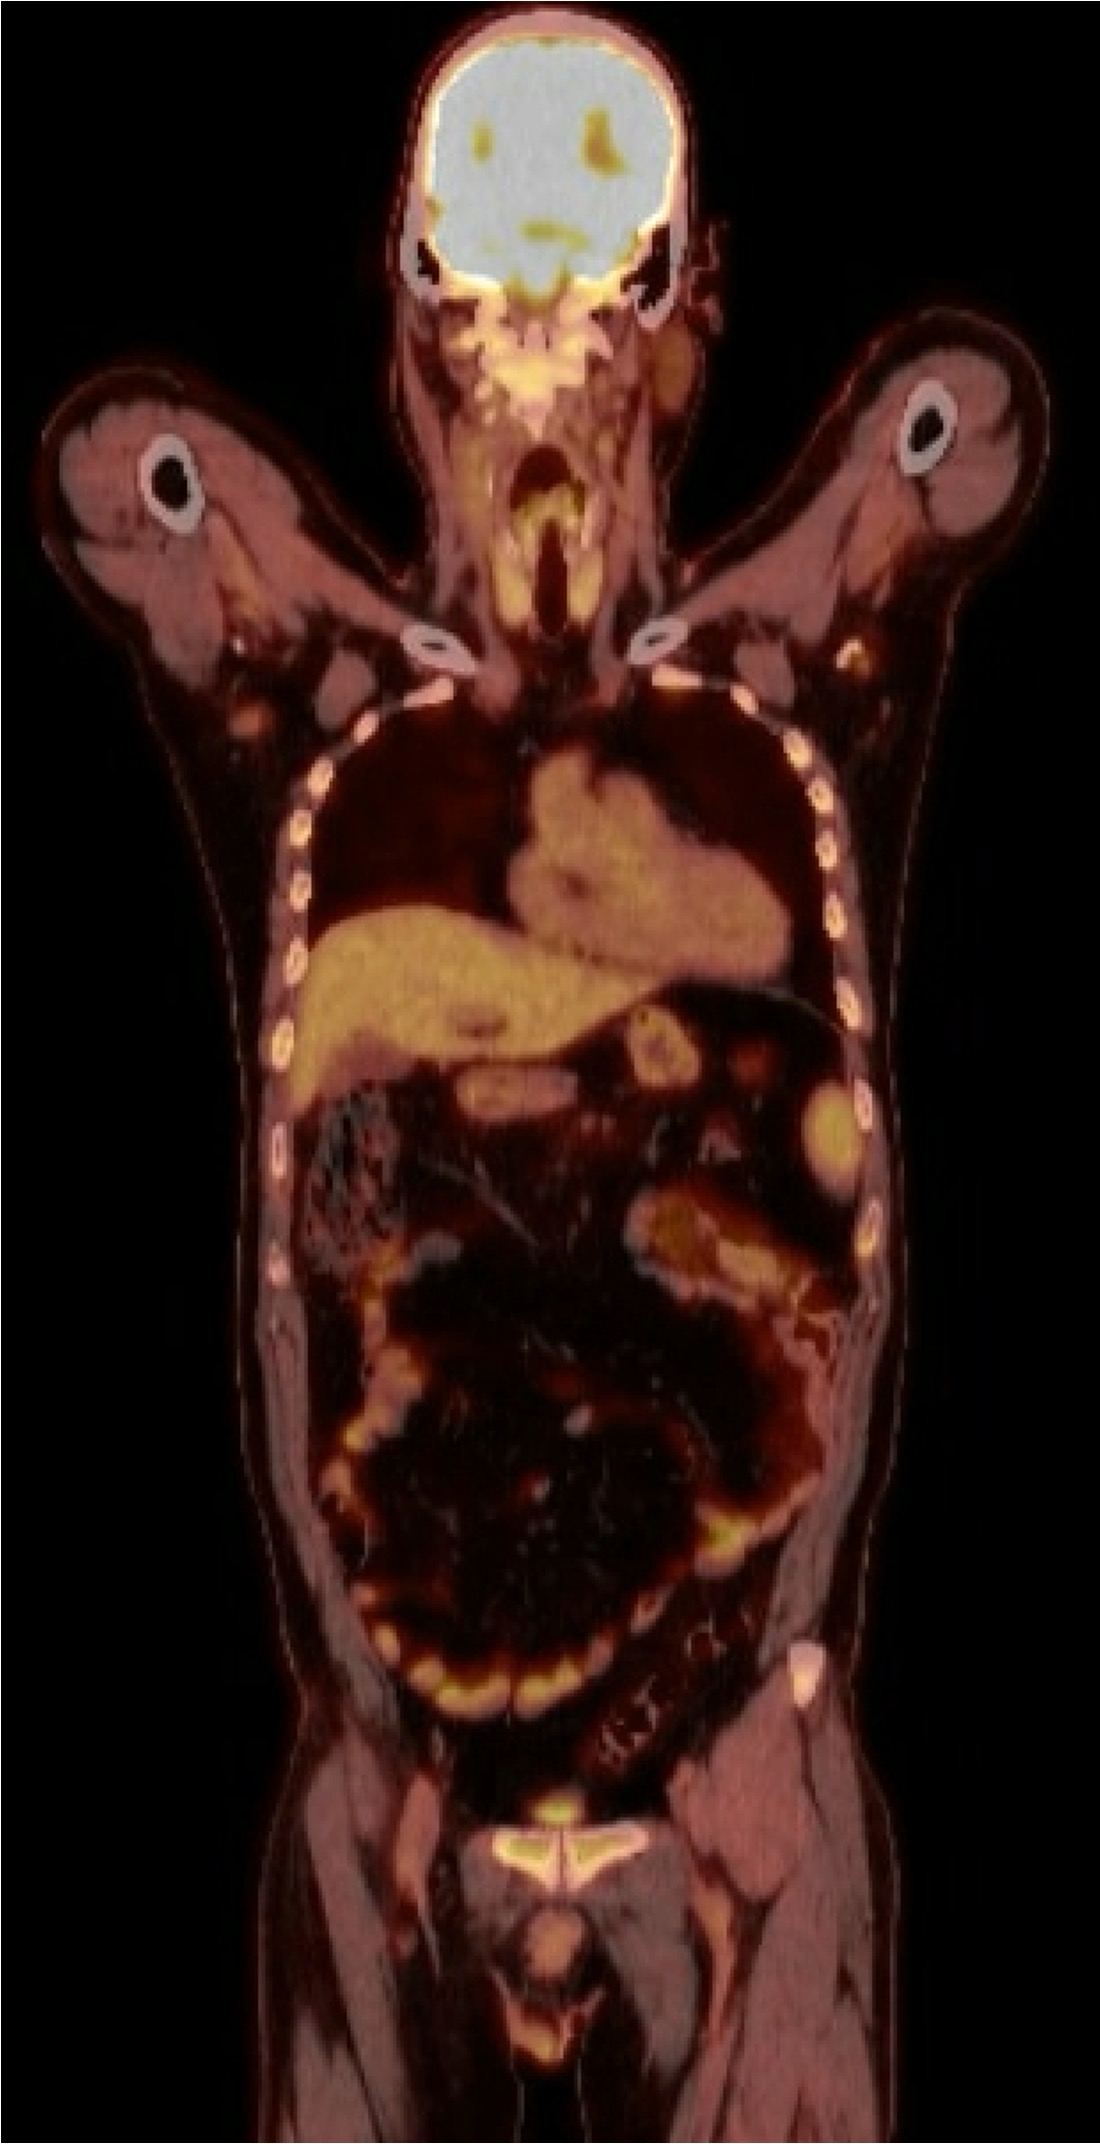

Case Presentation: A 50-year-old male with history of HIV with undetectable viral load on ART presented to the emergency department for evaluation of left eye blurriness, ptosis, and ophthalmoplegia. History was notable for emergency department and outpatient ophthalmology visits one month prior resulting in a diagnosis of cranial nerve six palsy. MR angiography was unremarkable. He developed difficulty opening his left eye and reported having weight loss over the past month. On exam, vital signs were within normal limits. Labs revealed uric acid 8.0 mg/dL and WBC 9.34 K/uL. Repeat orbital imaging showed infiltrative soft tissue throughout the cavernous sinuses. MRI of the brain and positron emission tomography revealed widely distributed lesions and lymphadenopathy throughout the brain, chest, abdomen, pelvis, and skeleton suspicious for malignancy. Bone marrow and lymph node biopsy revealed B cell lymphoma, CD10+/CD5- lambda monotypic. Cytogenetic analysis revealed IGH::MYC rearrangement. Pathology confirmed diagnosis of Epstein-Barr virus (EBV) negative Burkitt lymphoma (BL). Patient began chemotherapy with Etoposide phosphate, Prednisone, Vincristine sulfate (Oncovin), Cyclophosphamide, Doxorubicin hydrochloride (Hydroxydaunorubicin), and Rituximab (EPOCH-R). Follow up 6 months later shows continued response to therapies.